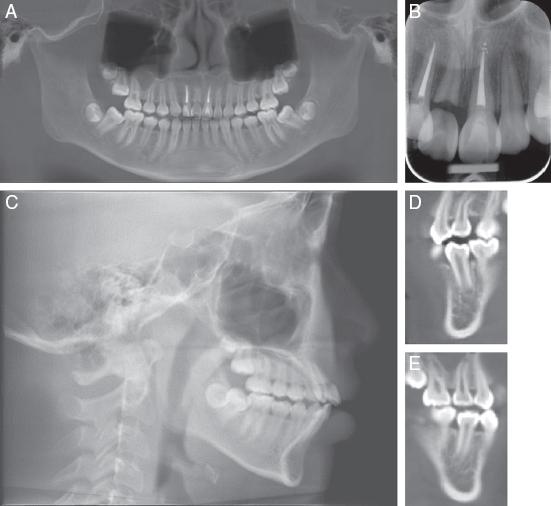

As a result of the trauma, the upper right central incisor (#11) was missing. The upper left central incisor (#21) and upper right lateral incisor (#12) were root canal treated and showed clinical and radiographic signs of ankylosis and replacement resorption (Figure 2A-D).

(A) Pretreatment dental panoramic radiograph. (B) Periapical radiograph showing resorption on the apical surfaces of #12 and #21. (C) Lateral cephalogram. (D) CBCT section showing developing tooth #45 with ¾ root length.